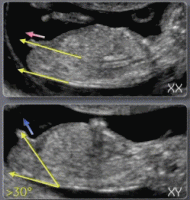

Sur cette photo tu vois bien la différence